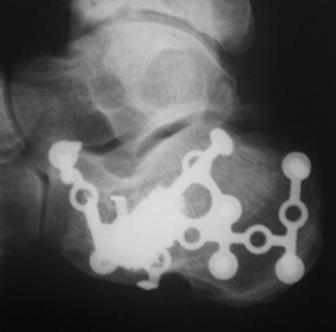

ЗДРАСТВУЙТЕ. ПОДСКАЖИТЕ ПОЖАЛУЙСТА 2 МЕСЯЦ НАЗАД Я УПАЛ С 4ГО ЭТАЖА-СЛОМАЛ ПЯТКУ. МНЕ СДЕЛАЛИ ОПЕРАЦИЮ, С ТАЗА ВЗЯЛИ КОСТЬ И ВСУНУЛИ В ПЯТКУ. ВРАЧИ ПРОМУЧАЛИ МЕНЯ ПОЧТИ 2 МЕСЯЦА И В ОКАНЦОВКЕ НЕ ДАЛИ ГАРАНТИИ ЧТО Я СМОГУ НАСТУПАТЬ НА НЕЕ И ЧТО ВОЗМОЖНЫ ЕЩЕ ОПЕРАЦИИ. СЕЙЧАС Я НАХОЖУСЬ ДОМА НА ЛЕЧЕНИИ С СПИЦАМИ В ПЯТОЧНОЙ КОСТИ. ВРАЧИ НЕ МОГУТ СКАЗАТЬ КОГДА Я СМОГУ ХОДИТЬ.ЧТО МНЕ ДЕЛАТЬ В ТОЙ СИТУАЦИИ?

Фото0046.jpg